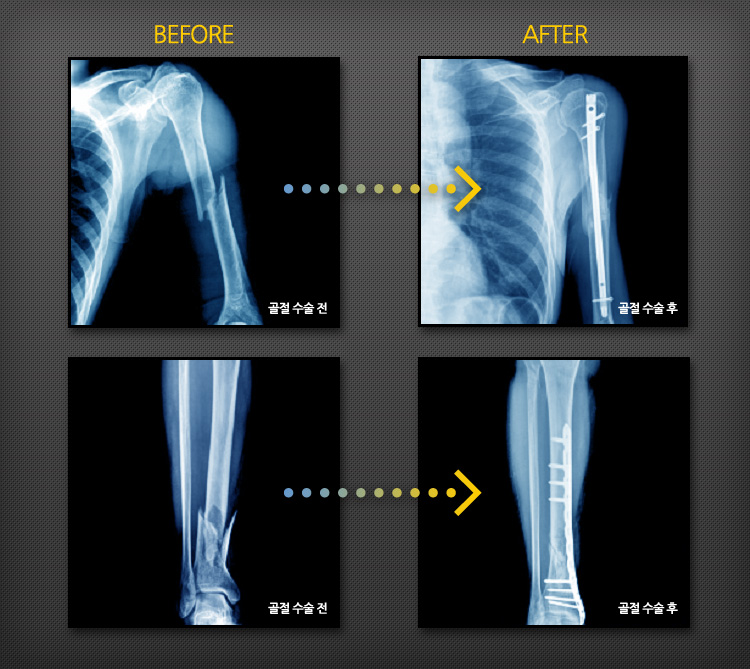

골절수술의 증례